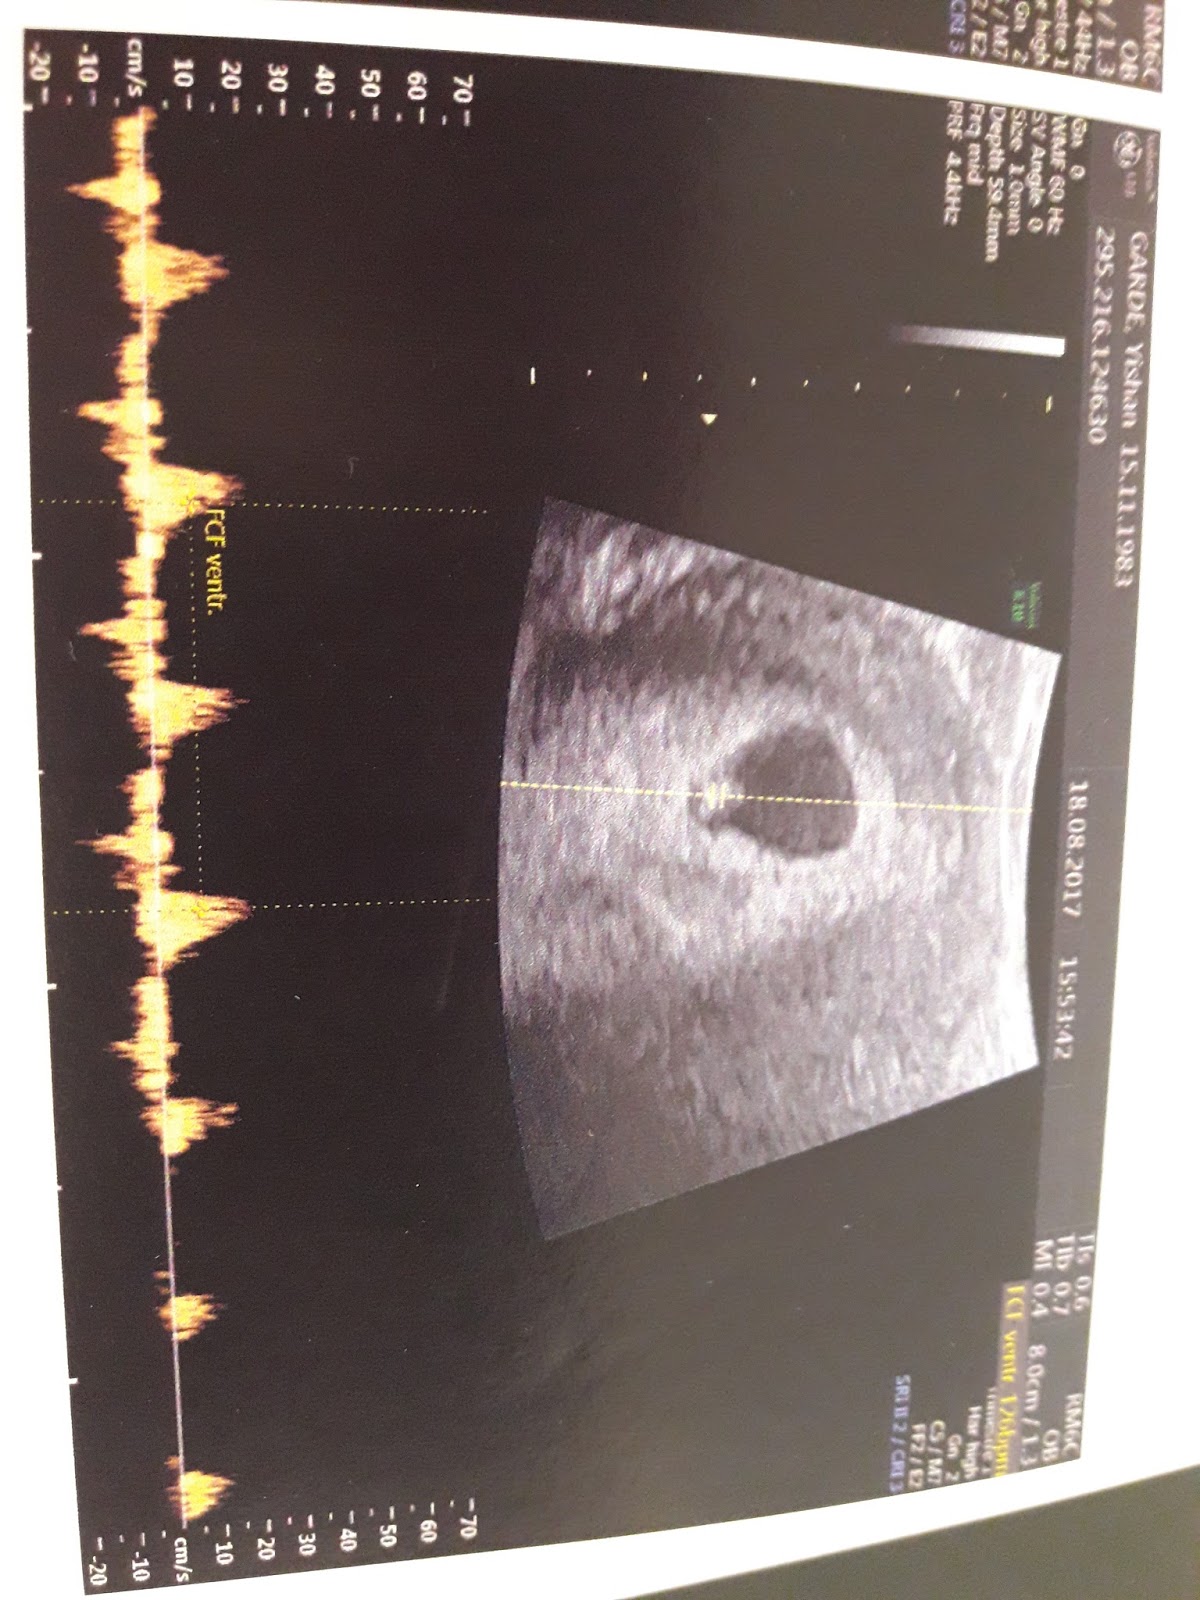

After 5/6 days of injections, we went for an ultrascan

and to our surprise (including the gynae's), there was a potential egg!

We were trying not to be too crazily happy when we saw the small bean

and get to hear the heartbeat!!